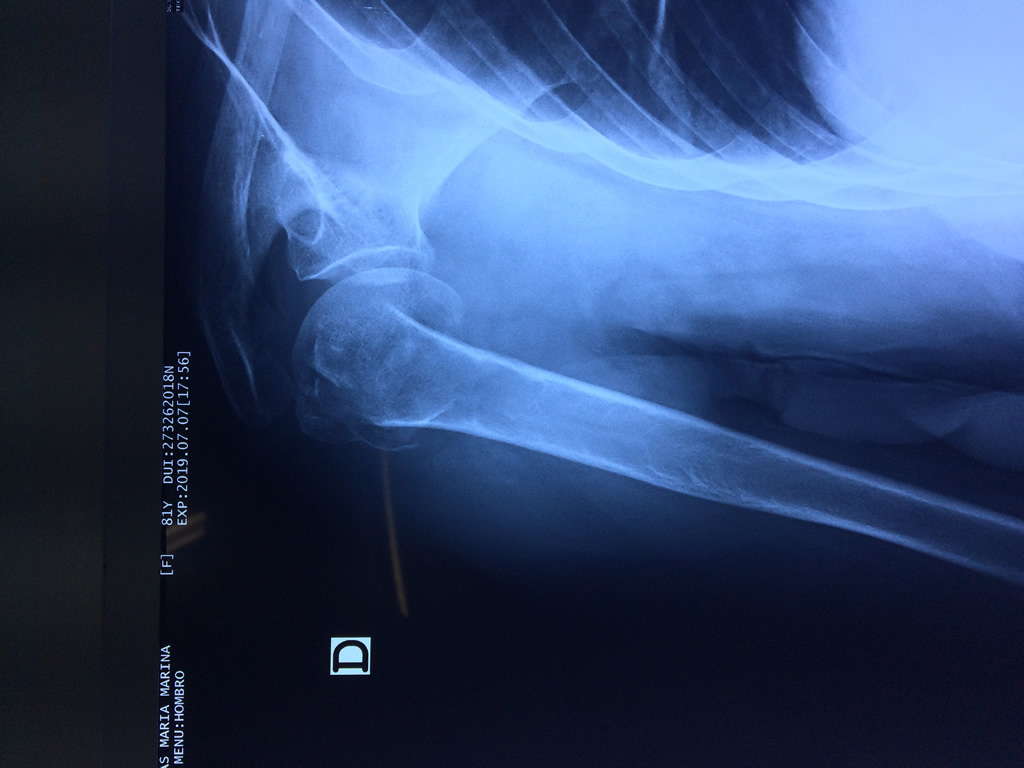

En anatomía humana, el hombro es la parte del cuerpo donde se une el brazo con el tronco. Está formado por la conjunción de los extremos de tres huesos: la clavícula, la escápula y el húmero; así como por músculos, ligamentos y tendones.

La principal articulación del hombro es la que une la cabeza del húmero con la escápula, recibe el nombre de articulación escapulohumeral y presenta dos superficies articulares, una de ellas corresponde a la cabeza del humero que tiene forma semiesférica y la otra es la cavidad glenoidea de la escápula, estas superficies están recubiertos por cartílago que permiten un movimiento suave e indoloro.